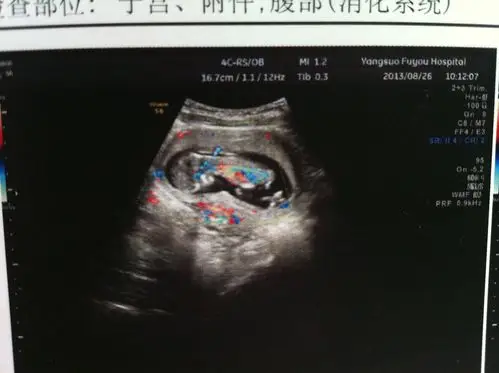

三个月的b超,有宝妈会看吗

三个月b超图像,大家帮忙看看是男孩还是女孩?非常感谢!

三个月彩超,心跳140/分,能看出男孩女孩吗

你好,这是孕三个月二十天的b超图,帮我看下男女!

网友:孕三个月胎儿已经发育成形,做nt的时候也会看到,可以通过身体